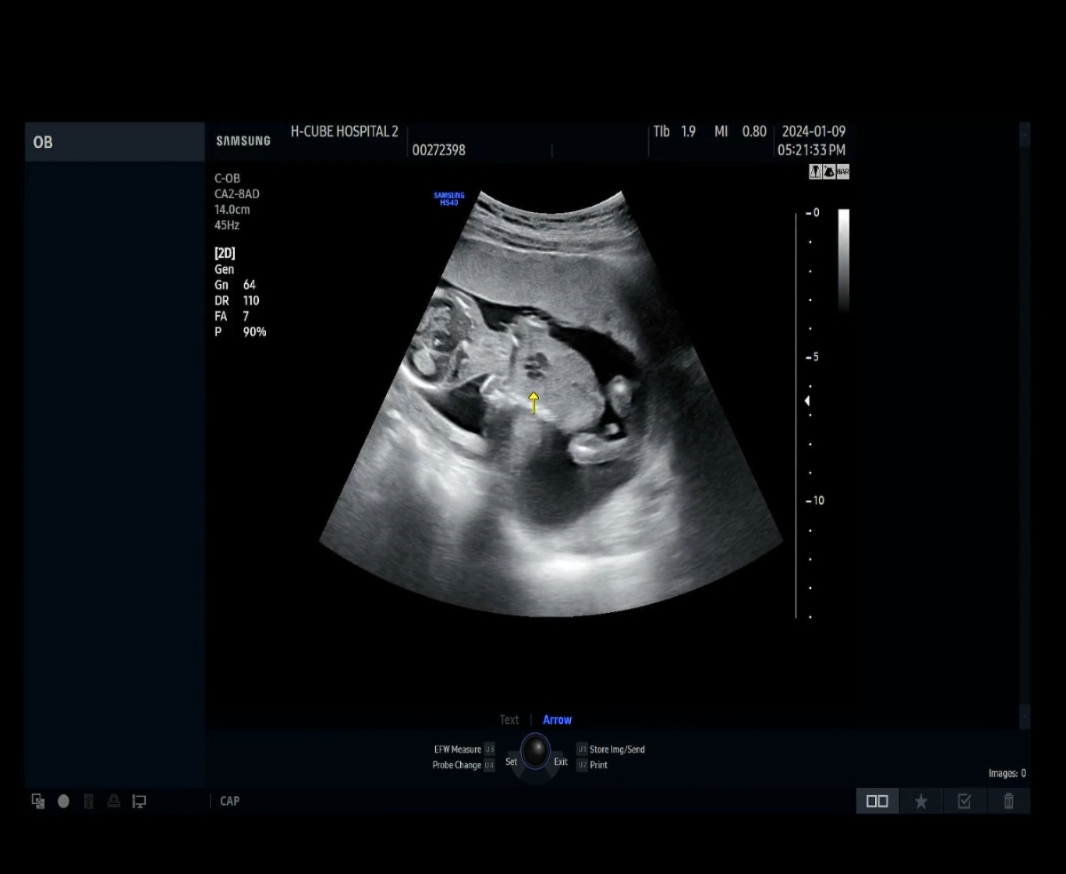

아들일까요??

초음파를 잠깐보고왔는데 탯줄인지 아들인지 넘궁금해지네용 선생님들 알려주세요~~

저만그렇게보이는게 아니겠죵?? ㅎㅎ

그래두 정확한건 슨생님이아시겠죠^^

다음주 정기검진날 여쭤봐야겠어용 ㅎ 감사합니당~~